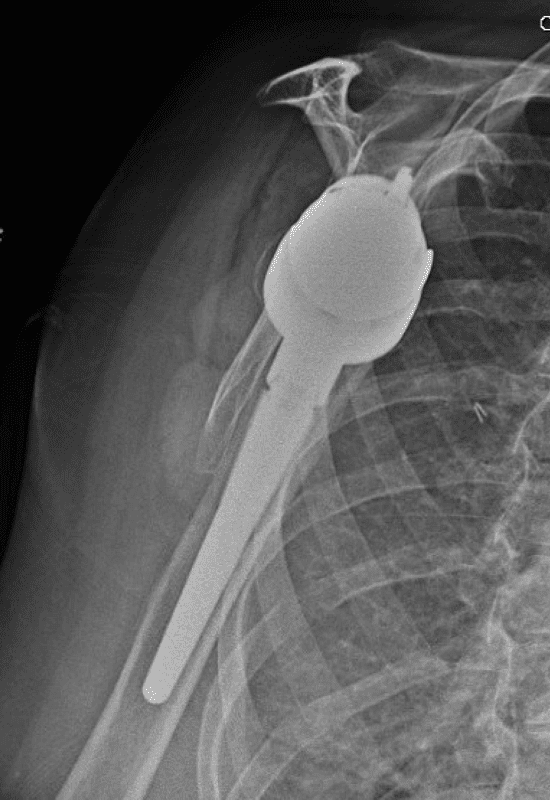

Lima, Augmented